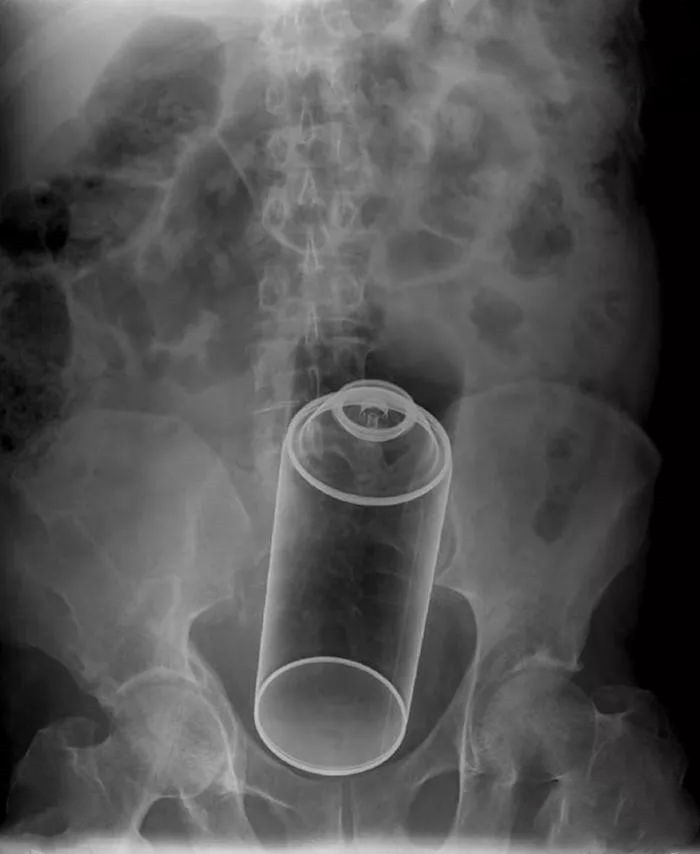

这家伙活生生把一罐喷雾也塞进了菊花。